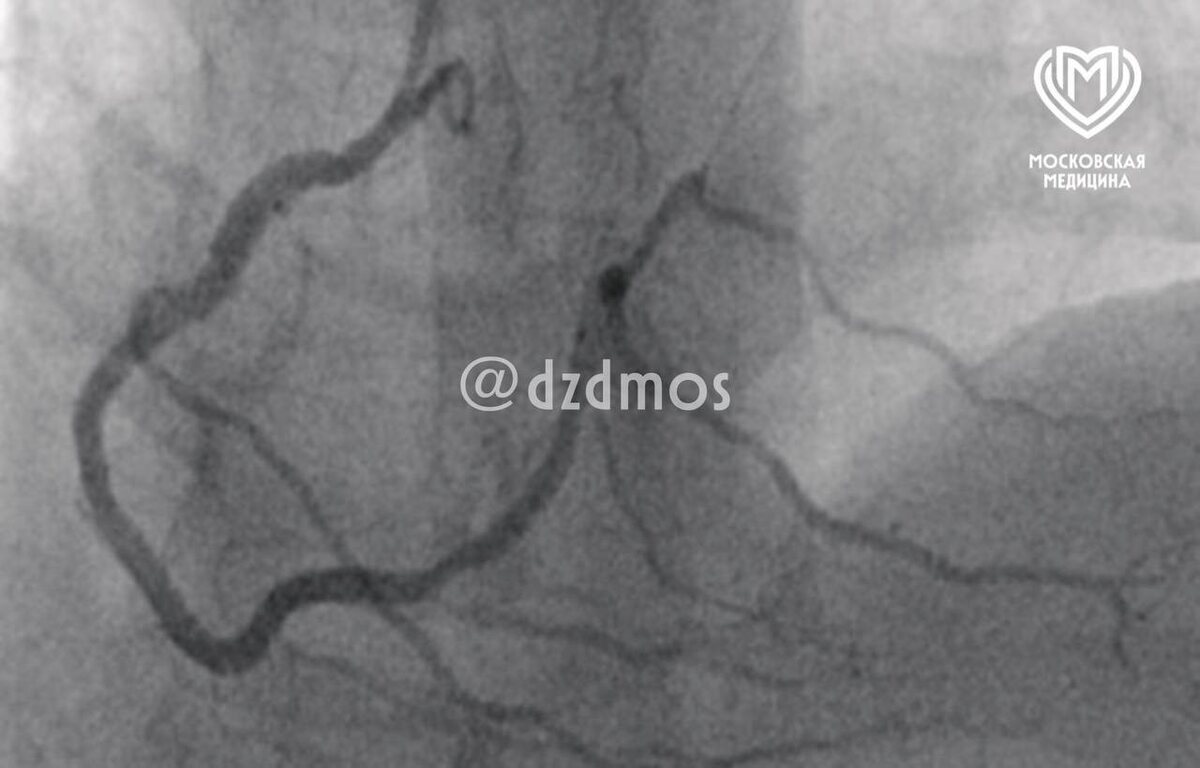

ΠœΠΎΡΠΊΠ²ΠΈΡ‡ съСл свинину ΠΈ столкнулся с Ρ€Π΅Π΄ΠΊΠΎΠΌ синдромом ΠšΠΎΡƒΠ½ΠΈΡΠ°, ΠΊΠΎΠ³Π΄Π° аллСргичСская рСакция ΠΏΡ€ΠΈΠ²ΠΎΠ΄ΠΈΡ‚ ΠΊ опасным Π½Π°Ρ€ΡƒΡˆΠ΅Π½ΠΈΡΠΌ Π² Ρ€Π°Π±ΠΎΡ‚Π΅ сСрдца.

К ΡΡ‡Π°ΡΡ‚ΡŒΡŽ, профСссионалы ΠΈΠ· скорой ΠΏΠΎΠΌΠΎΡ‰ΠΈ ΠΈ ΠΈ Π“ΠšΠ‘ β„–15 спасли ΠΏΠ°Ρ†ΠΈΠ΅Π½Ρ‚Π°. Он ΡƒΠΆΠ΅ Π΄ΠΎΠΌΠ° ΠΈ Ρ‚Π΅ΠΏΠ΅Ρ€ΡŒ вряд Π»ΠΈ Π±ΡƒΠ΄Π΅Ρ‚ ΡΠΊΡΠΏΠ΅Ρ€ΠΈΠΌΠ΅Π½Ρ‚ΠΈΡ€ΠΎΠ²Π°Ρ‚ΡŒ с рационом…